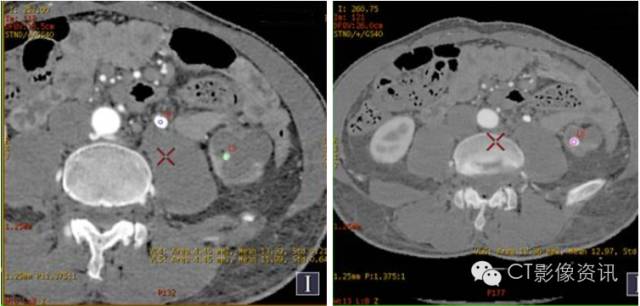

病史 男性,48岁,泌尿系结石患者复查。

在结石上分别放置ROI4(蓝色)、ROI6(粉色),得有效原子序数为13.30、12.97,二者非常接近,说明成分相似,对照泌尿系结石有效原子序数表,考虑这两个结石成分皆以草酸钙为主。而 ROI5(绿色)的有效原子序数为11.99,与ROI4、ROI6差别大,成分不同?

通过直方图可以发现,绿色柱状图并不是正态分布,跨度大(600—1300)且成分含量百分比相等(纵轴),也就是说ROI内成分并不单一,误差很大,需要调整ROI来得到有效的数据。

ROI4(蓝色)、ROI6(粉色)的能谱曲线几乎完全吻合,说明二者成分相同。